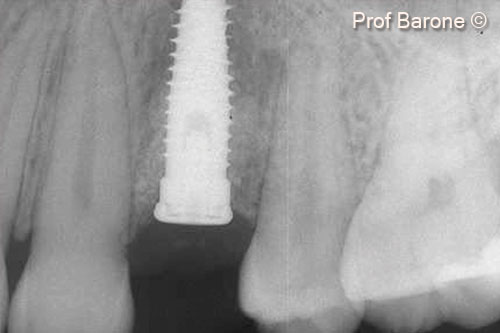

Một bệnh nhân nữ (27 tuổi) có biểu hiện nhiễm trùng cấp tính và mủ từ lỗ rò ở miệng.